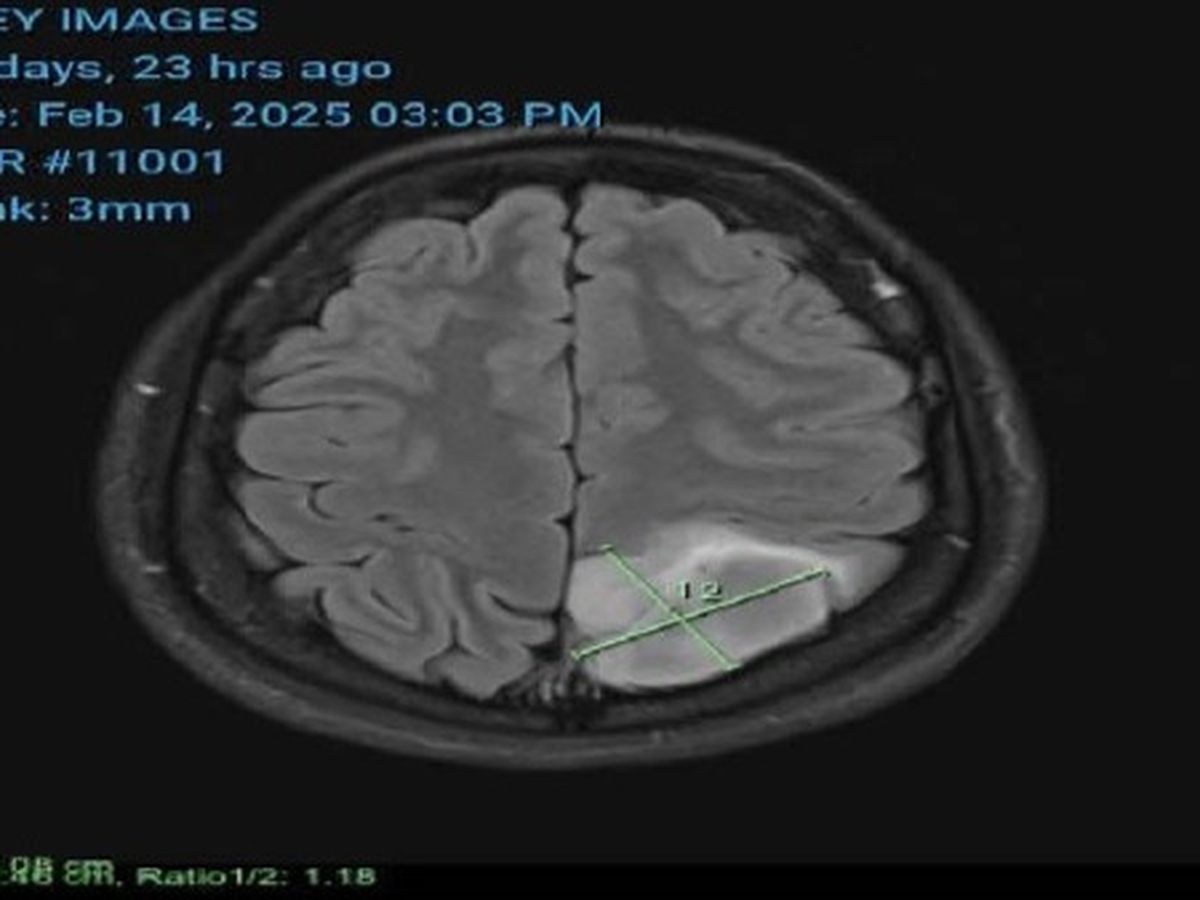

On the 17th of February, 2025. Our dear family member received horrible news that they had a 4x3.4cm tumour on their brain (Visible in the picture of this go fund me). This testing was the result of multiple health complications presented over the last couple of years. And most recently the recipient suffered seizures as a result of this tumour present on their brain.